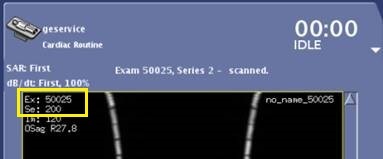

- The Motion Compensation preview images are displayed in AutoView while scanning but they are not stored in the Patient List. When displayed in AutoView, the series number is multiplied by 100. For example, if the original series is 2, the preview series, as displayed in AutoView, is 200.

Figure 5. AutoView series